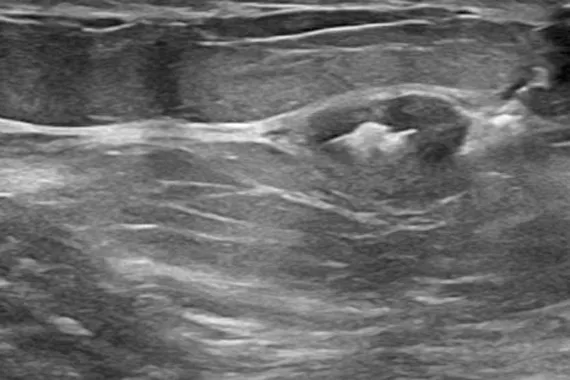

Designed to minimise movement,2 this marker is highly visible in ultrasound upon deployment and still highly visible at 6 weeks post-biopsy, crucial in case of future breast interventions.3 The marker consists of two pieces, a permanent marker and a bioabsorbable suture-like netting.

Image Gallery